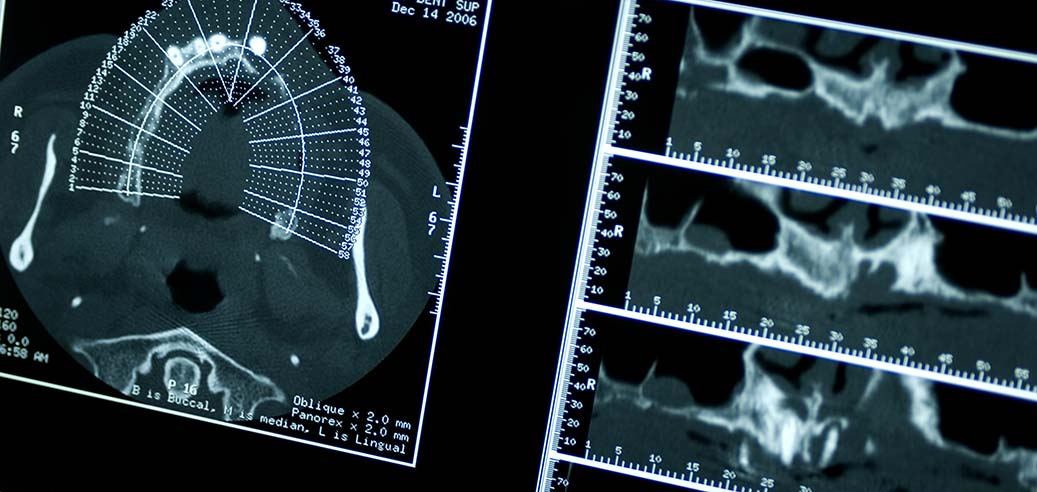

Our Madison, AL, dental office boasts state-of-the-art technology and is completely digital – from digital impressions and radiographs to digital x-rays and pictures. We have a 3D scan machine, an iTero scanner for digital impressions, as well as online patient portals and payment options for your convenience. See below for a breakdown of our current technology.